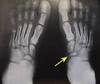

Ecchymoses

Grey turner’s

Flank ecchymoses

Cullen’s

Periumbilical ecchymosis (tracks up falciform)